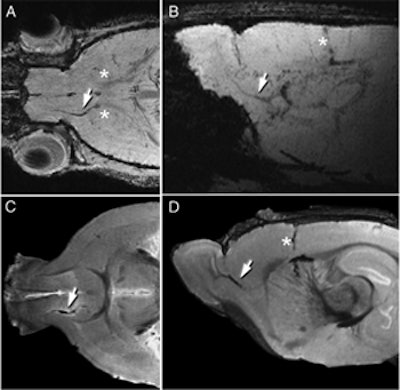

| MRI can be used to follow the migration of neuroblasts tagged with a ferritin-based reporter. Tagged cells are visible in each image (white arrows). Images courtesy of Carnegie Mellon University. |

In the current study, Ahrens and Iordanova employed the same technique as in the initial study, this time tagging the neuroblasts with the engineered ferritin. They incorporated the DNA sequence for the engineered metalloprotein into an adenovirus vector, which was then injected into the subventricular zone of a rat brain.

The adenovirus infected the neural stem cells, giving the cells the genetic instructions to begin producing the ferritin reporter. Iordanova then imaged the brain with MRI and found that she was able to follow the neuroblasts in real-time as they traveled toward the olfactory bulb and ultimately formed new inhibitory neurons. These results mirrored what had been observed in histology studies.